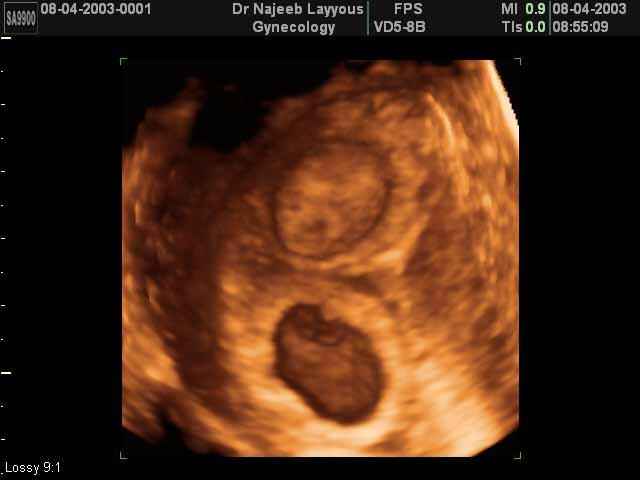

و هناك بعض التطورات التي تحدث في تكوين الجنين في الشهر الثالث من الحمل، و منها كما يلي :

- وضوح وجه الجنين بشكل بسيط .

- يبلغ وزن الجنين 26 جرام و يصل طوله إلى 10 سم.